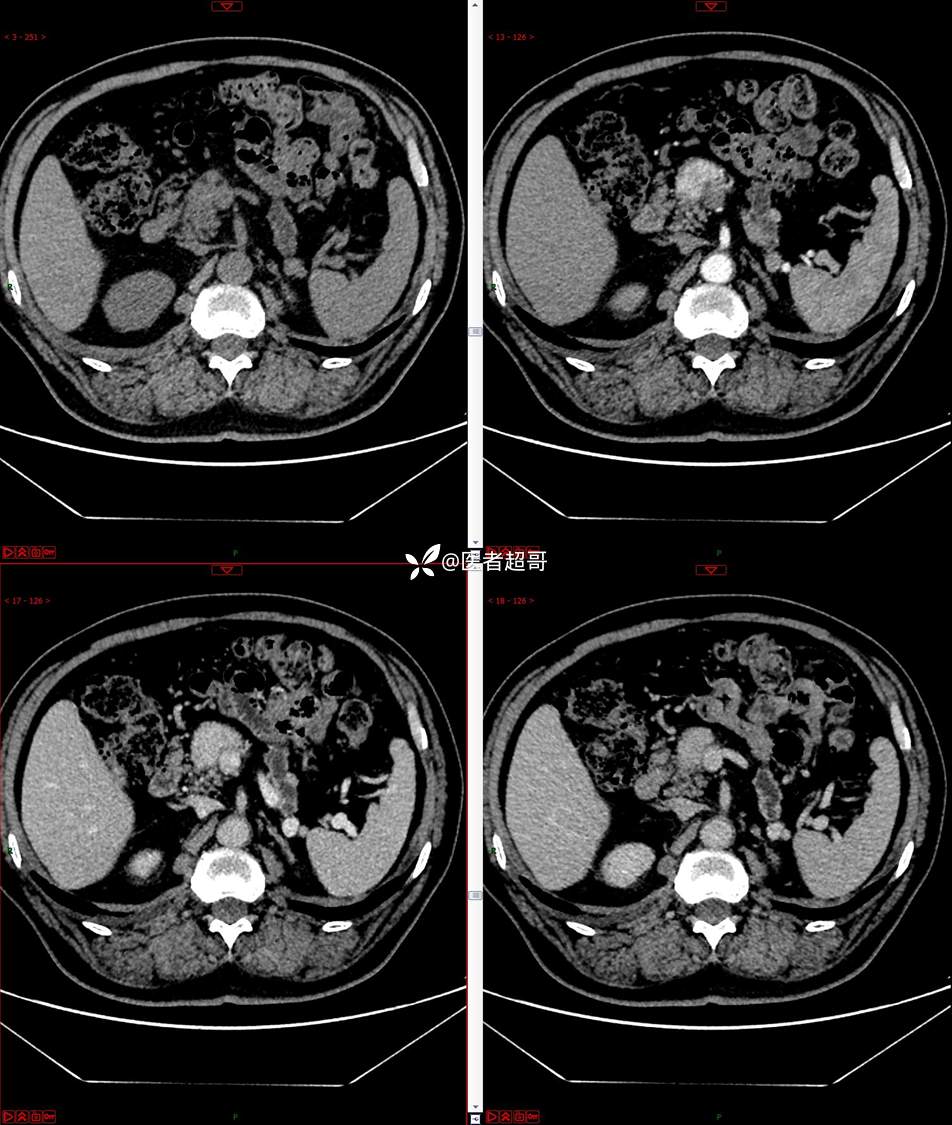

【影诊笔记677】查体发现胰腺占位性病变1周,细节决定成败,请诊断分析!

主 诉:查体发现胰腺占位性病变1周。

现病史:患者1周前在当地查体时发现胰腺占位性病变,无恶心、呕吐,无腹痛,无寒战、高热,无咳嗽、咳痰等异常不适,来我院门诊查上腹部CT平扫+强化:胰腺尾部异常密度灶。今为求进一步治疗,门诊以“胰腺占位性病变”收入院。患者自发病以来,一般情况可,神志清,精神可,普通饮食,二便正常,体重及体力无明显改变。